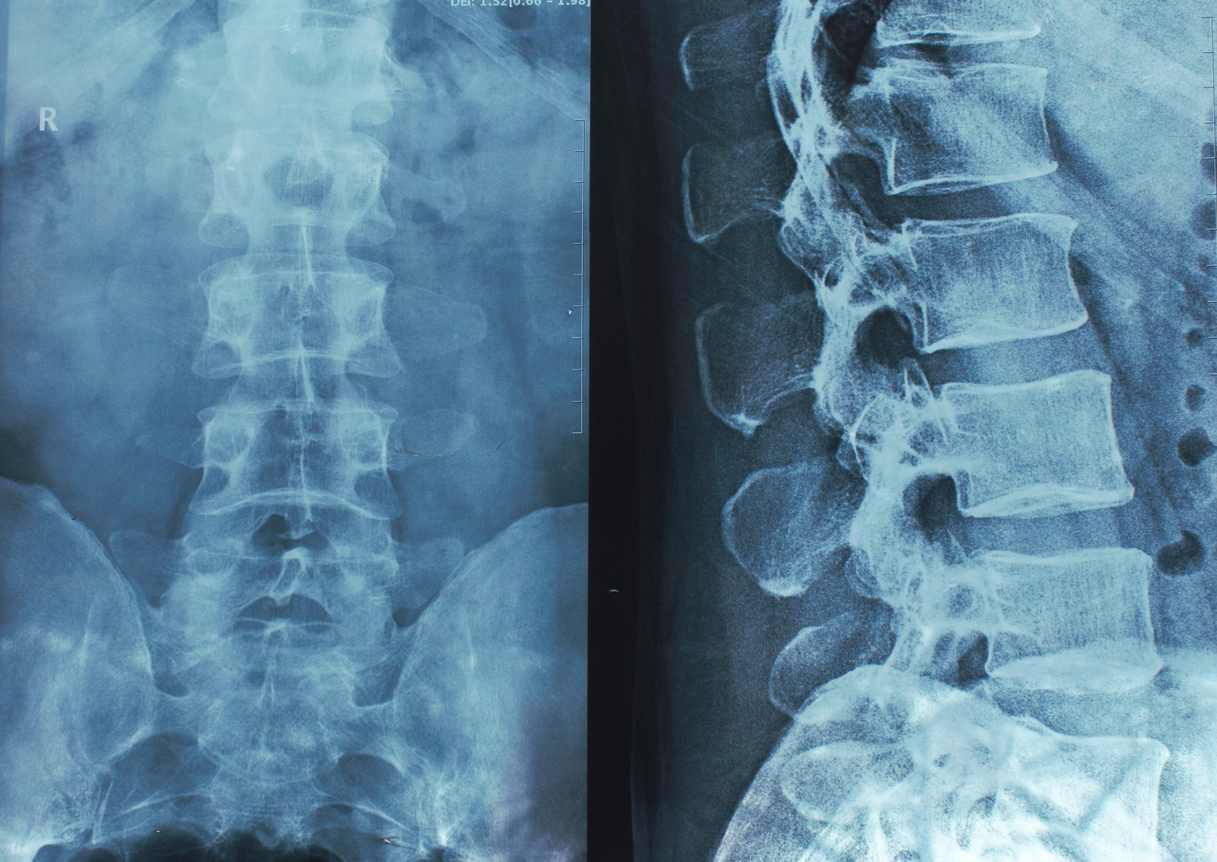

Медицинские снимки: рентген позвоночника сбоку